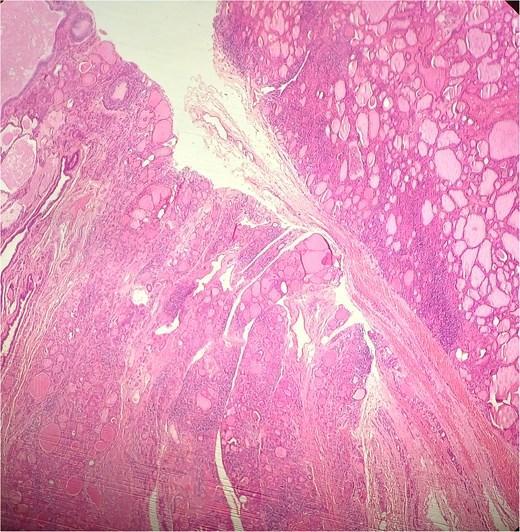

A 47-year-old woman with unremarkable medical history, presented with a 2 months history of neck mass along the midline. Physical examination revealed a 6 cm mobile, thyroid nodule without compressive symptoms. There was no associated erythema, fluctuance, tenderness or adhesion to adjacent structures. There was also no associated cervical lymphadenopathy. The rest of the physical exam was unremarkable. Laboratory tests including TSH, FT3, and FT4 revealed normal levels. On cervical ultrasound, there were a 62 mm left toto-lobar nodule classified as EU-TIRADS3, and an 11 mm right nodule, also classified as EU-TIRADS3. Fine-needle aspiration cytology concluded to a benign lesion classified as BETHESDA II. The patient reported respiratory discomfort in the supine position, leading to the indication for a lobectomy. Gross examination of the specimen revealed a toto-lobular nodule with a colloid appearance. It was well-circumscribed by a thin and regular fibrous capsule. The nodule measured 4 × 6 cm and exhibited areas of fibrous, whitish remodeling, as well as hemorrhagic and cystic changes. On microscopic examination, the nodule corresponded to a macro vesicular adenoma altered by fibrosis and hemorrhage. It was surrounded by a thin, regular, and intact fibrous capsule. However, at the periphery of the nodule, adjacent to the thyroid pseudo capsule, a 1.2 cm cystic ductal structure was observed. It showed pseudostratified ciliated columnar and squamous epithelial lining associated with thyroid follicles in the surrounding stroma (Figs 1 and 2). These thyroid follicles were bland with no papillary nuclear atypia or invasion (Fig. 3). The cyst was filled with a thin eosinophilic material (Fig. 4) Lymphocytic thyroiditis of mild severity was identified in the rest of the thyroid tissue. Based on these findings, the diagnosis of macro vesicular thyroid adenoma with ITTGDC and lymphocytic thyroiditis was made. After the surgery, the patient developed temporary dysphonia.

HE × 4 incidental finding of cystic duct structure in the adjacent thyroid gland tissue.